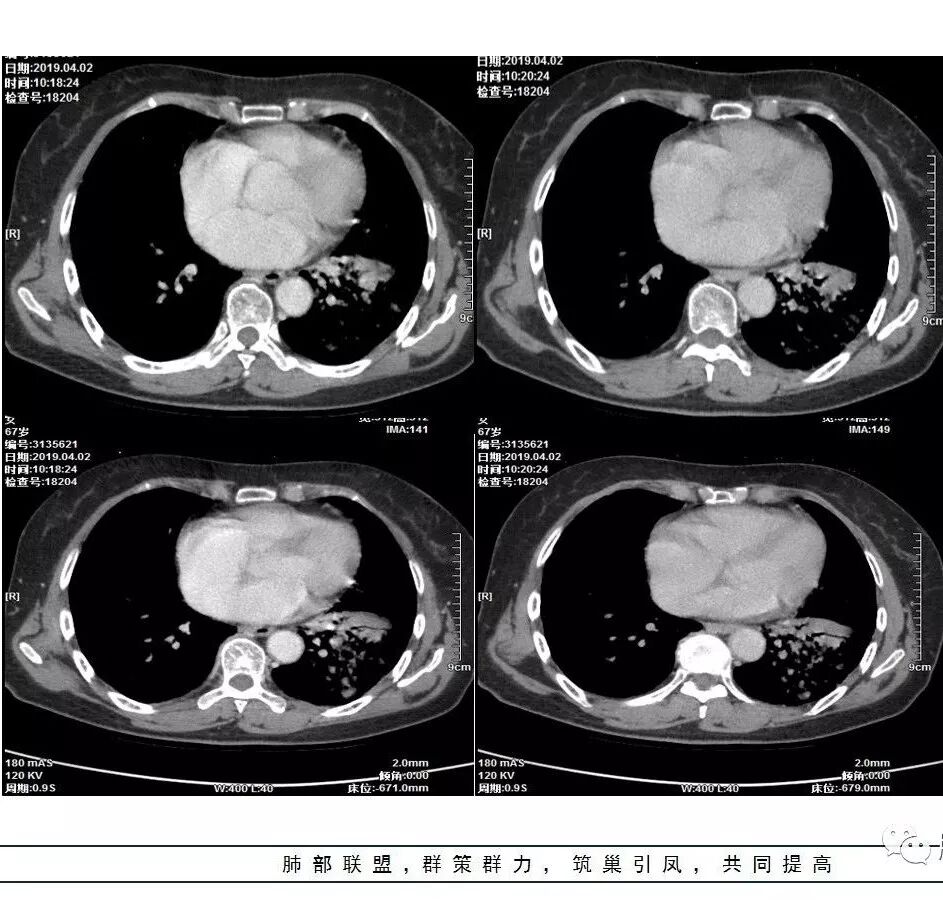

这是老问题:1、肺门区软组织密度影较弥漫;我们常规鉴别的就是结核?鳞癌?既往我们群里基本这两方向。2、弥漫的淋巴结钙化,加上马赛克灌注。马赛克灌注的原因是两个,一个是肺动脉的,一个就是小气道的问题。我们看增强的区域,没有看到栓塞,所以我倾向于小气道的问题,就是弥漫气道病变,慢性气道病变要考虑。我怀疑有没有淀粉样变性累及气道壁改变的可能。淀粉样变性是一个继发性病变,结核也可以,粉尘也可以。

实变部分强化很明显,怎么解释合理呢

结核强化可以这样吗?

南边:

肉芽肿期强化明显

肉芽肿是一个病理的概念,是炎症后期的修复,它的本质其实是迟发型过敏反应引起的炎症,在免疫应答中主要是一些巨噬细胞、上皮细胞来起作用,但是里面有非常丰富的毛细血管,所以这类病变强化很明显,影像上一般是结节状、团块状、大片状,整体有膨隆,边缘也有收缩,肉芽肿是一大类,影像有时很难区分,尘肺、结节病、淋巴瘤样肉芽肿都可以。常见的是炎性的,多见于结核,细菌性感染后期引起的类似op样,影像统称肉芽肿类病变,鉴别炎性还是恶性,要根据边缘、形态、周围结构及内部坏死情况。

今天这个病例有个明显的支气管狭窄,我倾向炎性,主要是和钙化淋巴结相关的,可能是继发的淀粉样变性。到底是什么感染,结核还是其他。我想看看复查后这个淋巴结,有没有突入到支气管腔内,如果有,他是继发于炎症的(比如中叶综合征,就是周围淋巴结压迫支气管,因为钙化淋巴结比较硬,支气管壁扛不住压力,突入支气管腔内,导致管腔狭窄,我们也称为结石征),如果没有,就和淋巴结关系不密切。之前有一例淀粉样变性的,淋巴结弥漫钙化,一种罕见的浆细胞型的CD。